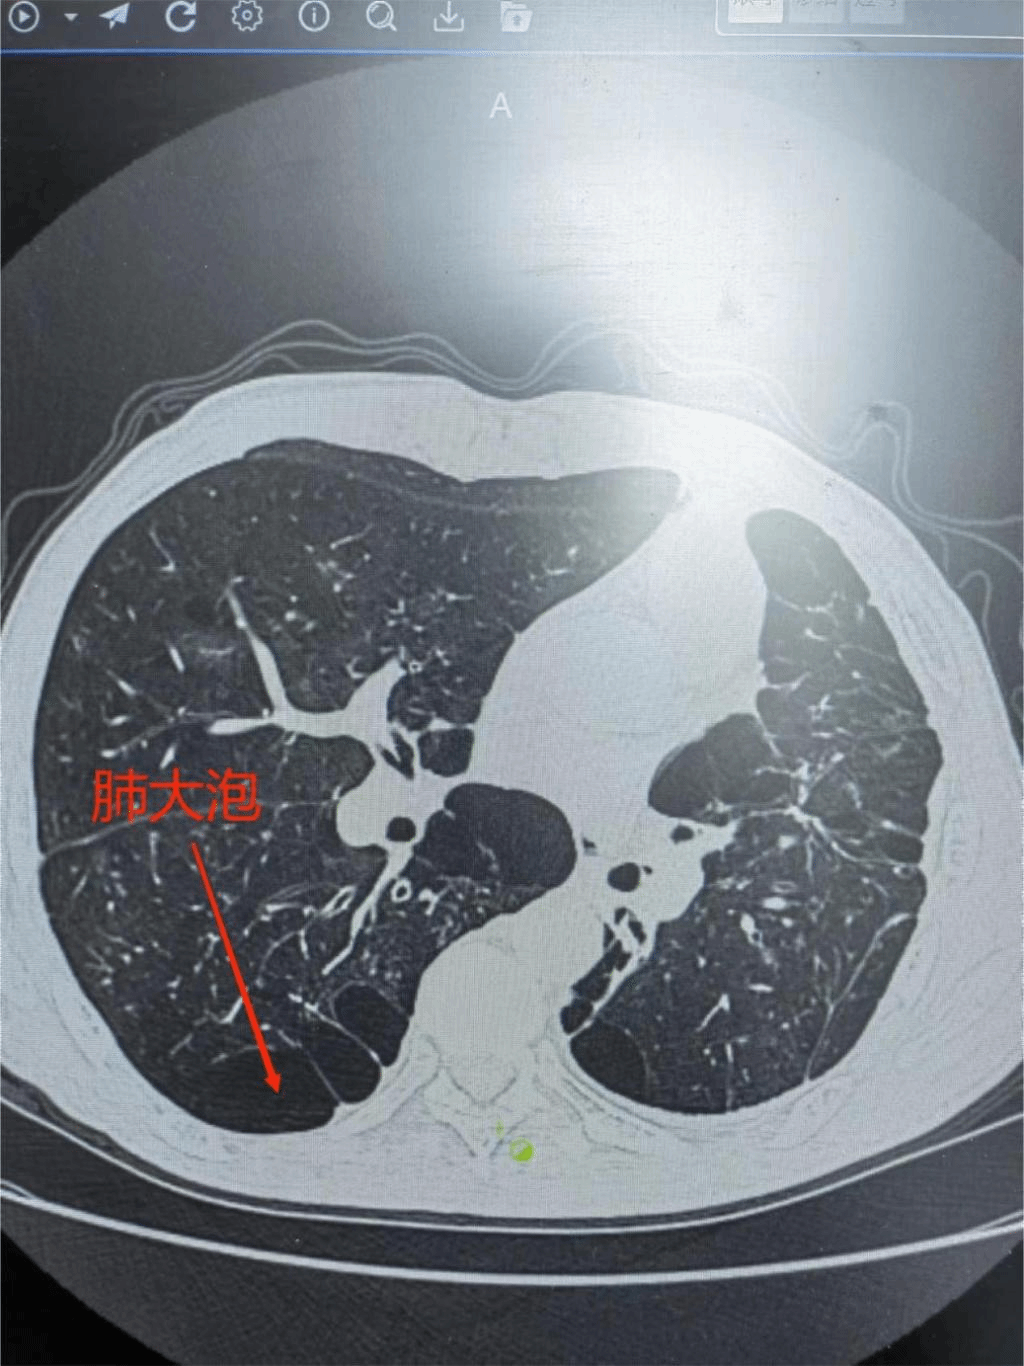

1月29日九江学院第二附属医院呼吸内科付云杰主任团队在胸外科张毅博士、麻醉科李成涛主任的协助下,成功为一例重度慢阻肺患者成功实施经无痛支气管镜双肺EBV活瓣肺减容术,一次性为患者处理了双侧肺大泡。术后患者即可起床活动,饮食照常,完全无痛,胸闷、气喘症状得到明显缓解,效果立杆见影。这是我院第二例支气管镜单项活瓣肺减容术,也是九江地区首例双肺支气管活瓣肺减容术。标志着我院支气管镜介入技术迈入新台阶,将造福更多九江乃至周边区域的患者!